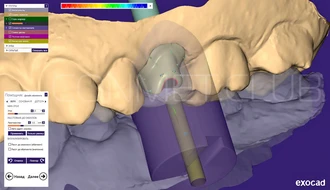

В программе BlueSky Plan были сопоставлены данные КЛКТ и внутриротового сканирования, и проведено планирование операции дентальной имплантации с последующим созданием хирургического направляющего шаблона. Совмещение изображений КТ и внутриротового скананирования позволяет достичь максимальной точности планирования и нивелировать цифровые шумы неизбежно возникающие при КТ исследовании.

Процесс моделирования в программе Exocad. Если кликнуть на снимок, то видно, что в программе присутствуют все компоненты Конмет, включая премиллы последнего поколения.

Индивидуальный абатмент полностью смоделированный в программе Exocad. Официальную библиотеку можно скачачать на сайте Exocad.com или обратиться на Конмет.

Смоделированный в программе Exocad индивидуальный абатмент размещен в виртуальном холдере Cam программы MillBox. Отчетливо видно, что вся моделировка была произведена с учетом геометрии премилла Конмет.